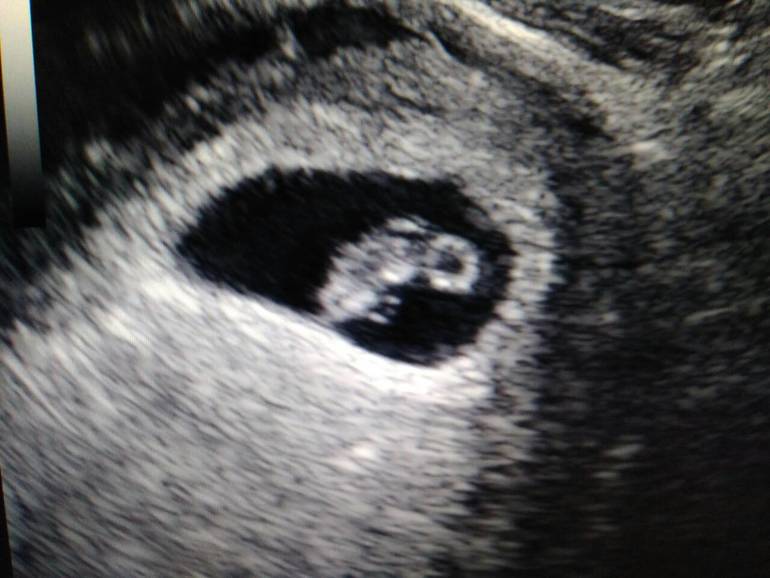

Я БЕРЕМЕННА !Сходила я на узи 😍 😍 😍 😘 😘 😘

Нам 7 нед и 4 дня ЖМ =2,8мм, КТР =12мм CБ+

Я счастлива!!!! На узи увидев как бьется сердечко моего малыша - разрыдалась от счастья!!!! 10 лет стараний не прошли зря!!! Девочки боритесь за свое счастье, не опускайте руки, все получится!!!! 🤗 Спасибо за вашу поддержу и ваши советы!